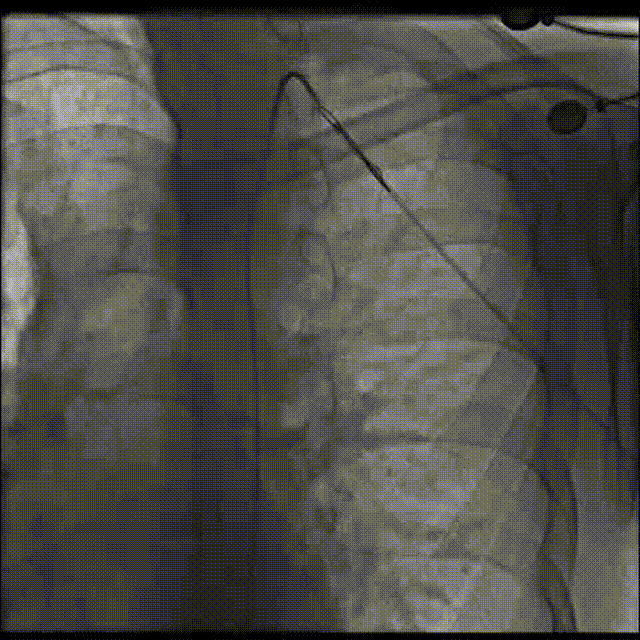

弓离断处送入39mm Cheatham-Platinum覆膜支架,选用20mmNuMED BiB球囊扩张

释放覆膜支架

术后造影显示离断处通路正常,无残余压差。

术后造影